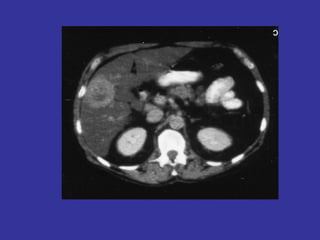

• Tomografía (TAC-TEM): posee menor precisión para las

valoraciones anteriores.

•   Presenta la ventaja de realizar un estudio completo

abdomen, pelvis, y tórax para valorar la extensión a

distancia del cáncer.

•   TAC: precisión T 53-94%, N 54-70%

TAC

Tumor      (T)             53-75%

Ganglios (N)               57-72%

Evaluación local limitada.

Identifica metástasis.